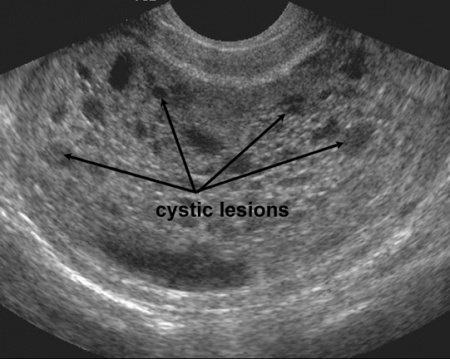

Case Study: Molar Pregnancy | Case Studies | POCUS.org

Case Study: Molar Pregnancy | Case Studies | POCUS.org www.pocus.org

Molar Pregnancy - WikEM

Molar pregnancy - WikEM www.wikem.org

molar ultrasound snowstorm wikem findings